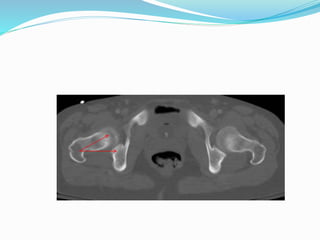

DİSLOKASYON

 Tkp sonrası ortalama olarak %3 olarak görülmekte

 Primer implantasyon sonrası en sık görülen erken

komplikasyonlardan